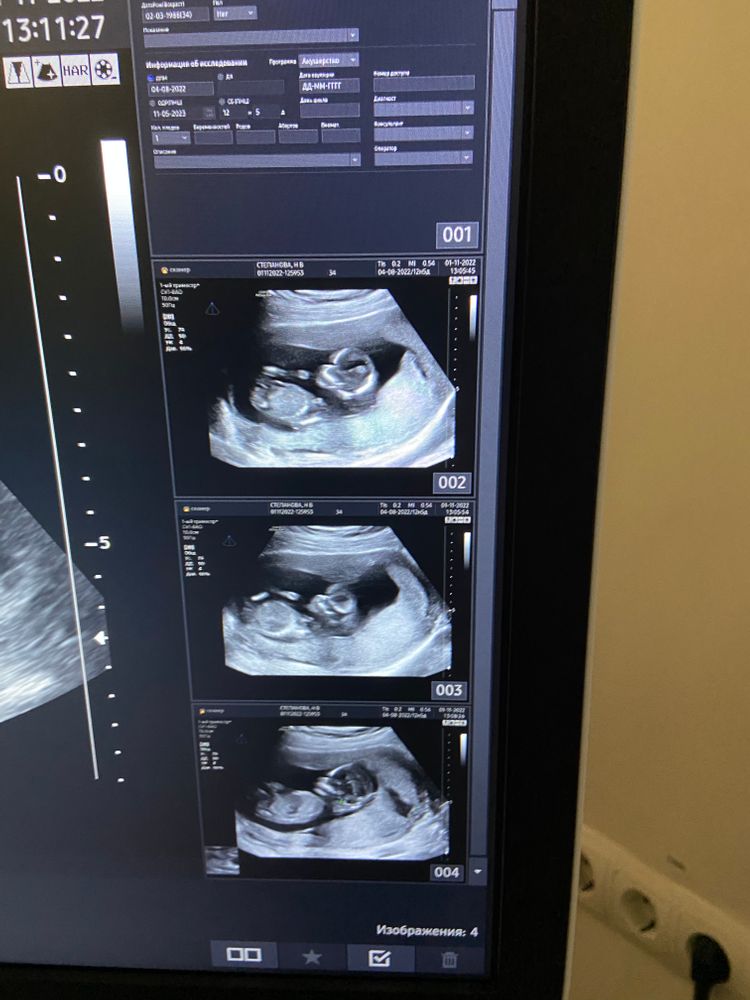

1) первый скрининг. Проходил в перинатальном центре (7 роддом)

все у нас хорошо, есть особенность строение хореона каверна ( полость между ворсинами хориона с током крови) необходимо наблюдать изменить ее нельзя… гематома… от неё остались какие то ошмётки которые даже не вынесли в диагноз. Ребёнок опережает срок на неделю по узи

На фото видно эту каверну справа щель большая… как и положено сдала кровь на определение рисков. Результат пришёл хороший.